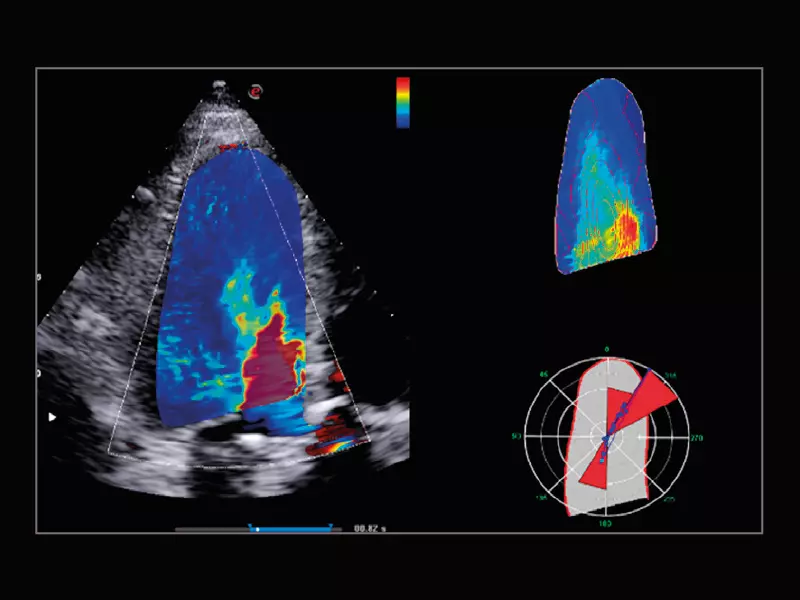

MyLab™9 Platform - XStrain4D technology for volumetric heart assessment by coronary territories

MyLab™9 Platform - XStrain4D technology for volumetric heart assessment by coronary territories

MyLab™9 Platform - Ultra-sensitivity Colour Doppler for precise visualization pulmonary veins

MyLab™9 Platform - Ultra-sensitivity Colour Doppler for precise visualization pulmonary veins

MyLab™9 Platform - Tissue Velocity imaging to quantify septal velocity and dyssynchrony

MyLab™9 Platform - Tissue Velocity imaging to quantify septal velocity and dyssynchrony